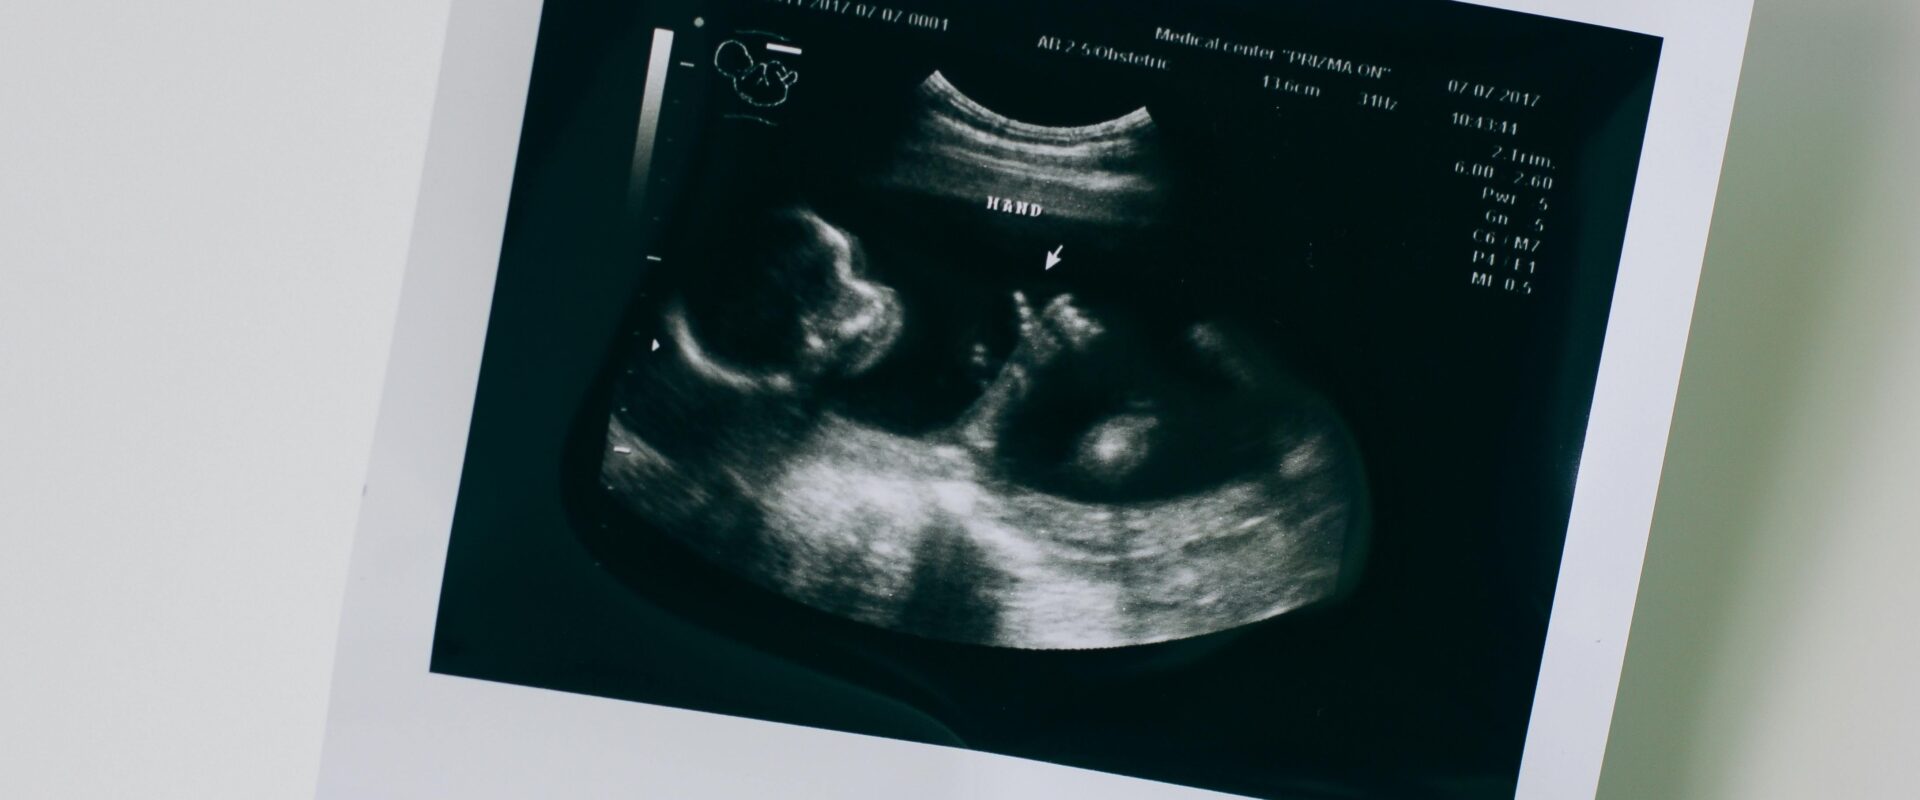

¿Te traumaron con el feto ingeniero? Desmitificando la narrativa de propaganda antiaborto

TweetLinkedInSharePrintPin Ciudad de México.- Entre los símbolos persistentes y más populares de las ideas antiaborto … Sigue leyendo ¿Te traumaron con el feto ingeniero? Desmitificando la narrativa de propaganda antiaborto